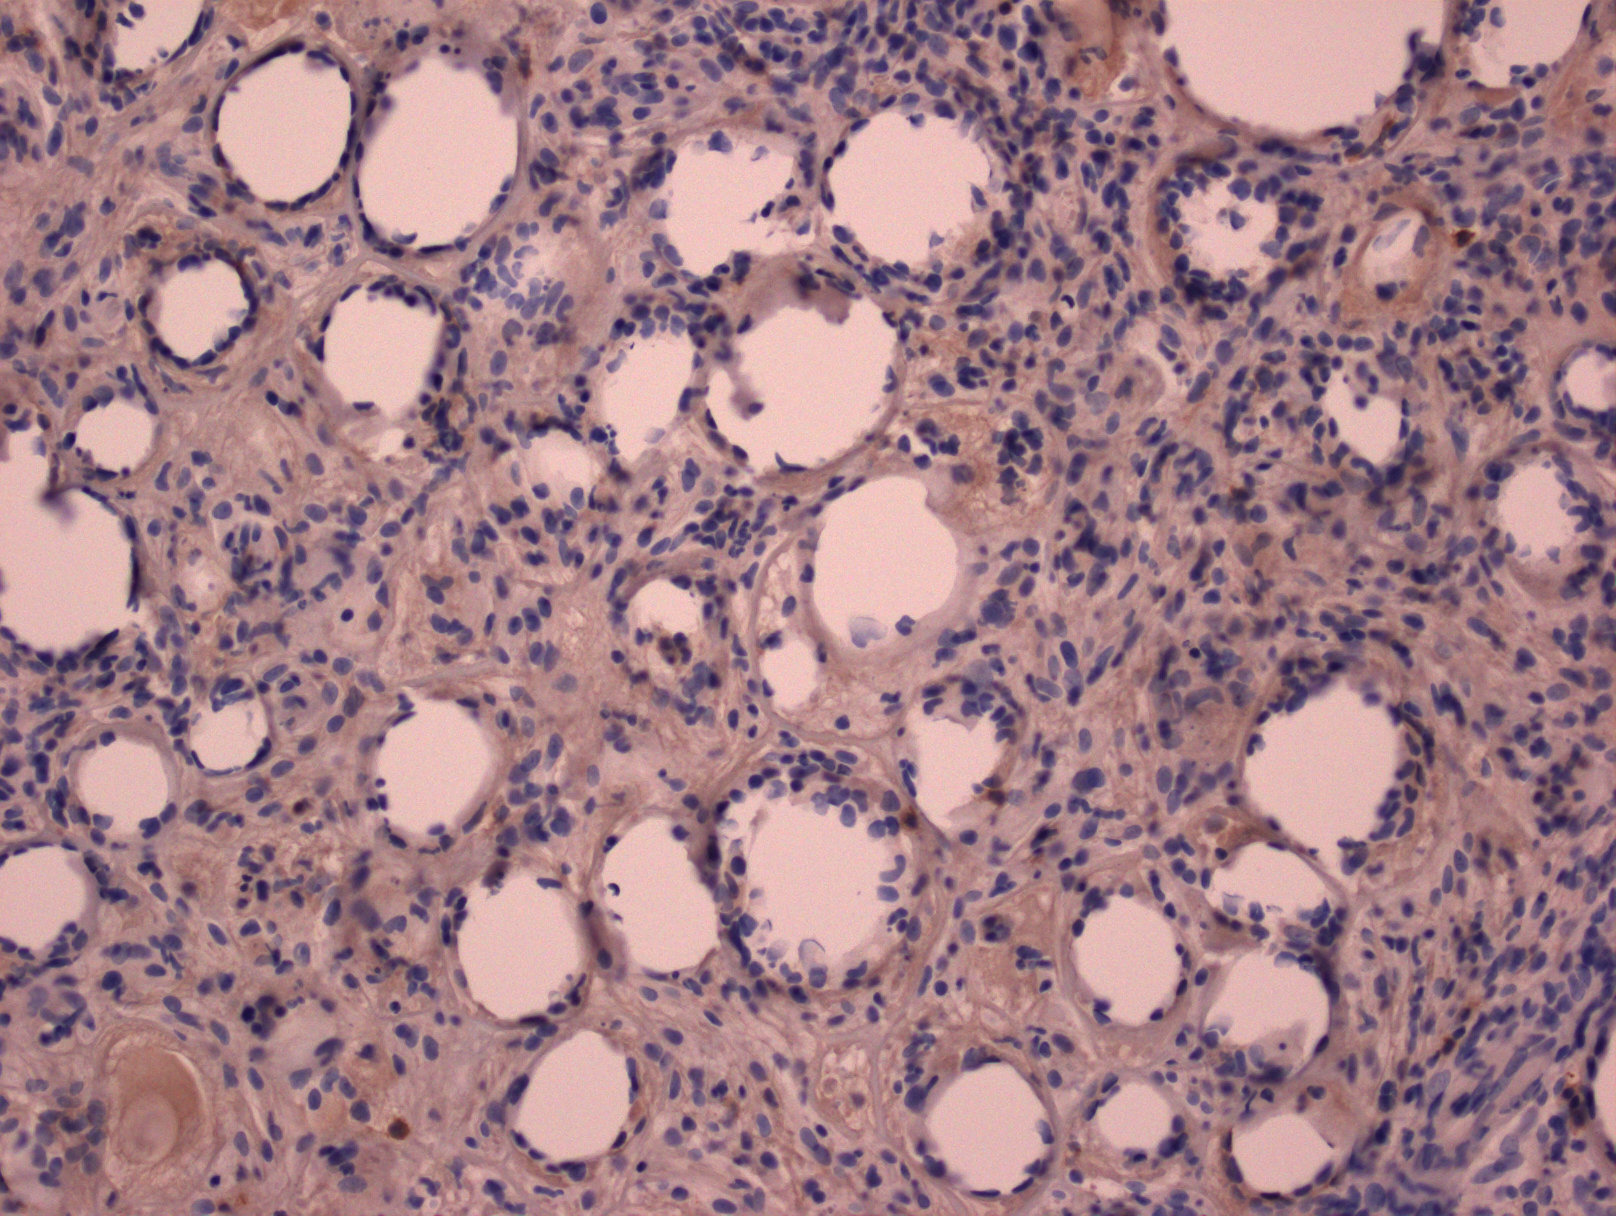

4. 免疫表型:肿瘤细胞 CD3+,通常 CD8+/CD4-,细胞毒分子+,βF1+,TCR-δ1-,CD56-